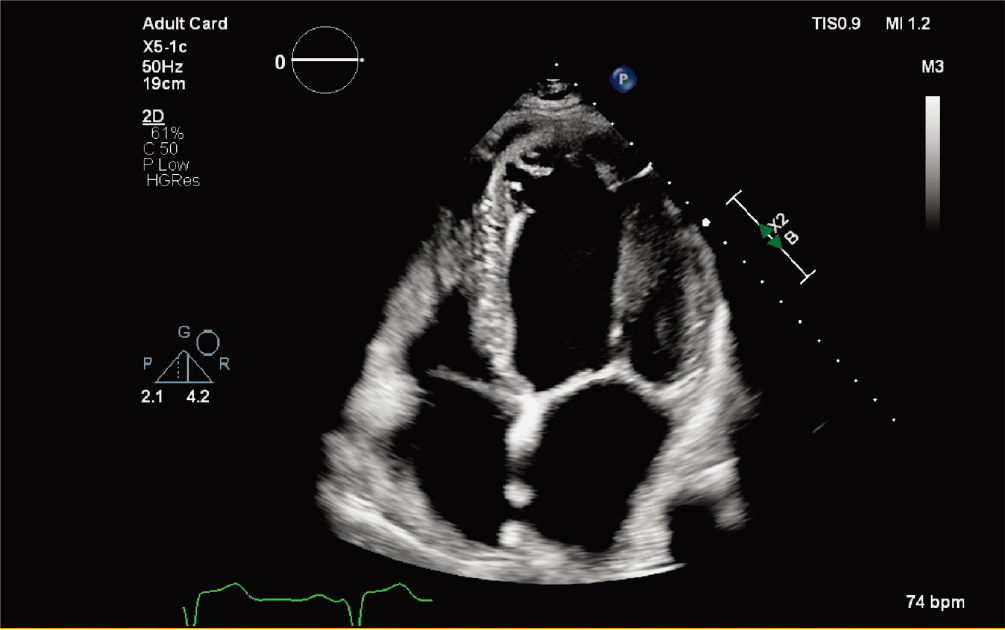

X5-1c探头

X5-1c 探头配备 nSight Plus,有助于优化 TTE 成像 |

X5-1c t探头的动态心脏模型 |

X5-1c 探头进行自动节段性室壁运动评分指数 |